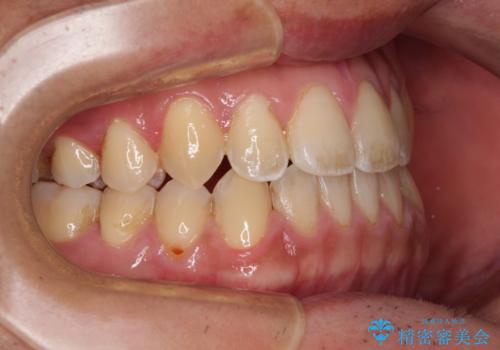

- 前歯のデコボコを気にして来院された患者様です。

歯列としてはワイヤー装置でもインビザラインでも対応可能でしたが、インビザラインが苦手とする上顎側切歯(真ん中から2番目の歯)の舌側転位が顕著でした。

治療の確実性を上げるために、インビザライン開始前に上顎のワイヤー装置にて舌側転位を解消し、その後インビザラインにて矯正治療を行うこととしました。